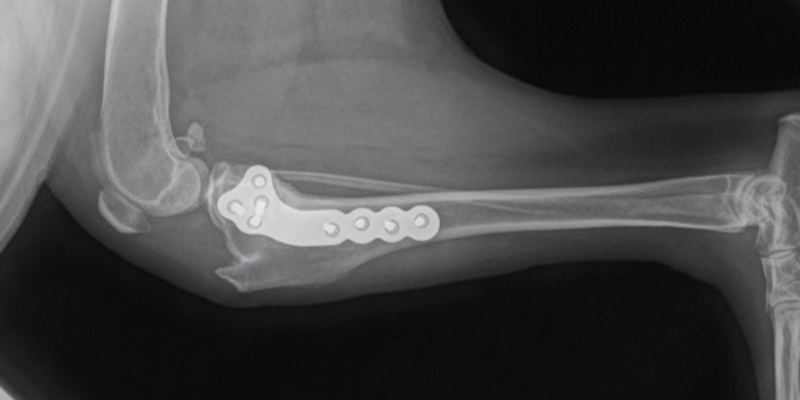

• zlomeniny končetin, pánve